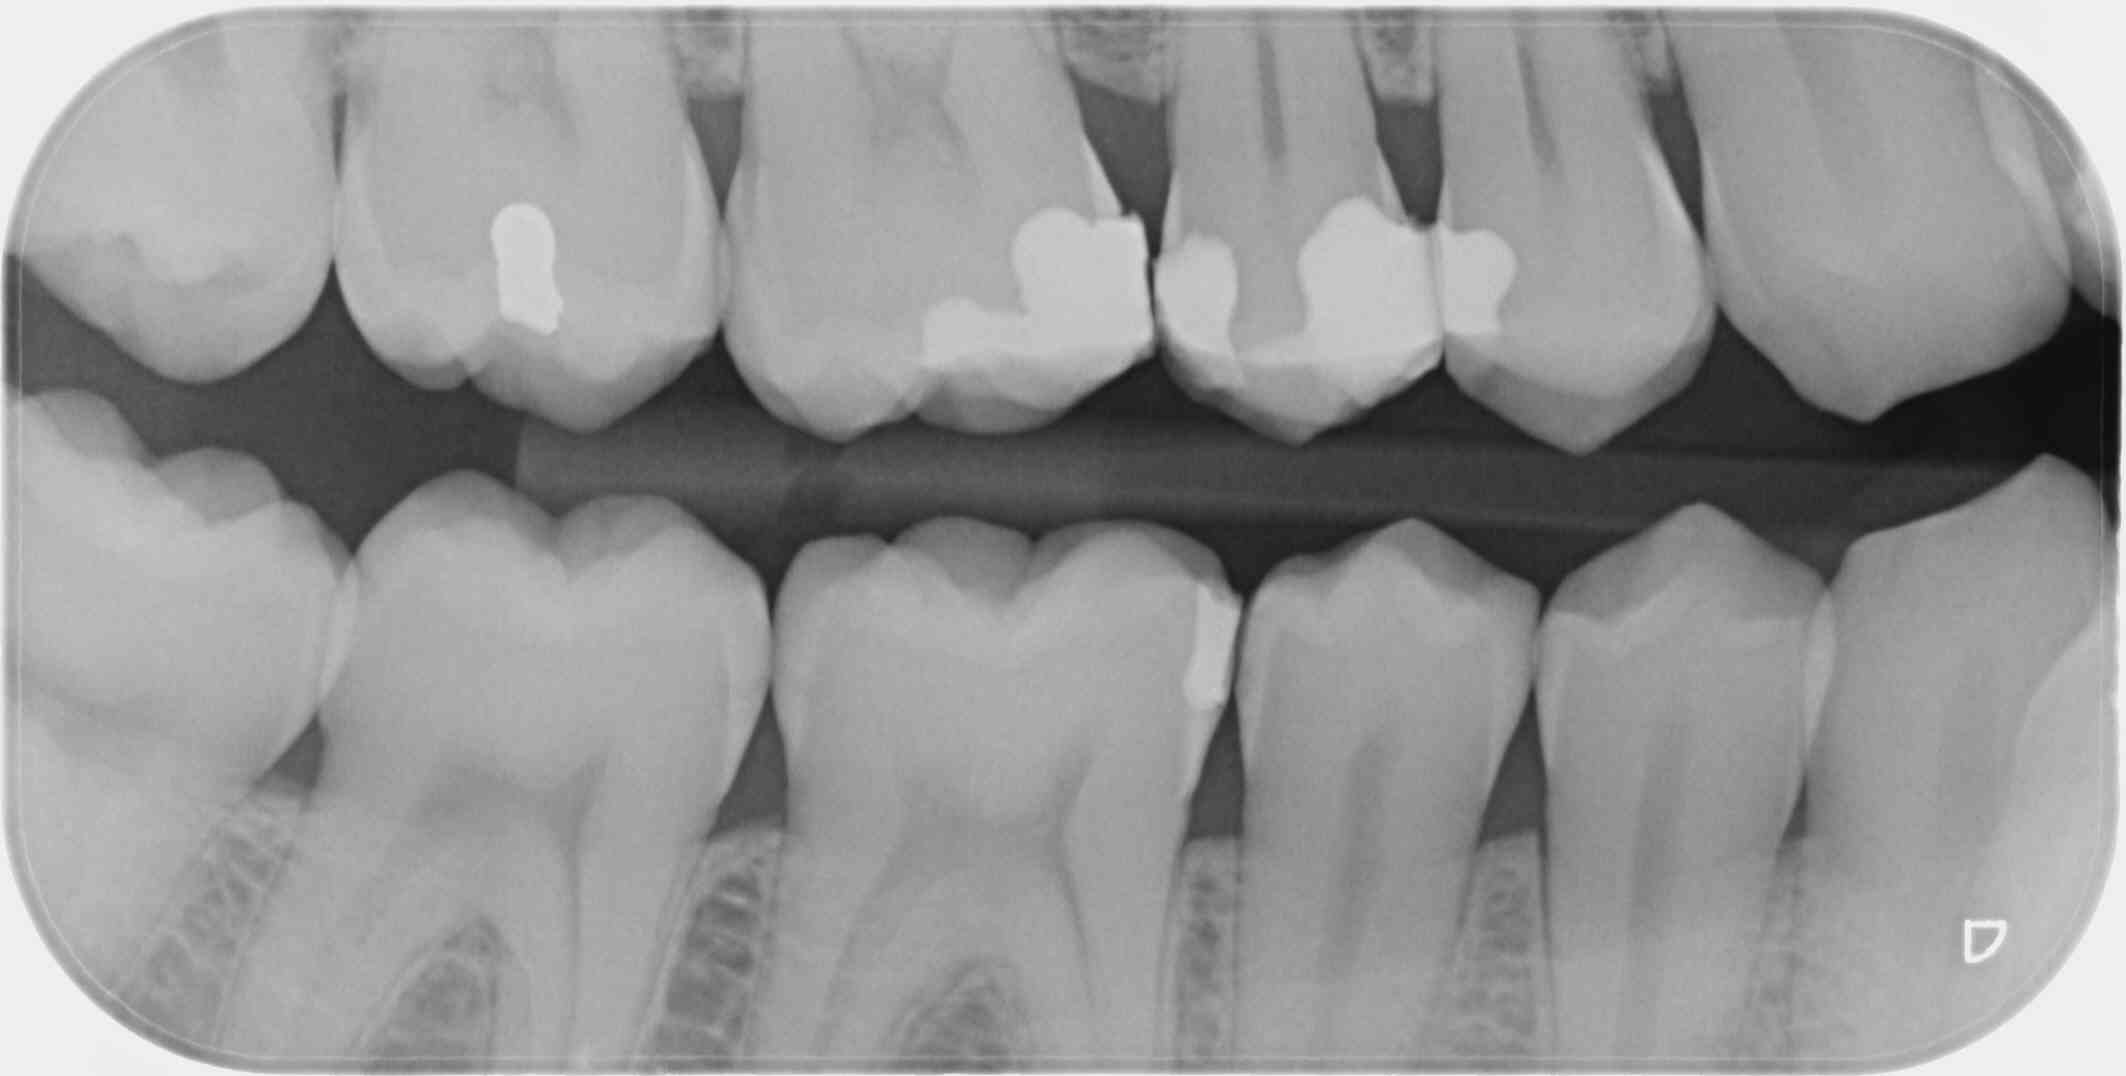

C'est une faille de la CCAM qui permet, avec un peu de mauvaise foi, de coder 4 secteurs avec seulement 2 clichés, le nombre de clichés n'étant pas précisé dans le libellé.

1 radio (au singulier) en bite-wing secteur 1 et 4 = 7.98€ (HBQK389, 2 secteurs mais 1 seul cliché)

2 radioS (au pluriel) en bite-wing secteurs 1, 2 , 3 et 4 = 31.92€ (HBQK443, 4 secteurs, plusieurs clichés sans précision sur leur nombre).

T'es con d'utiliser des films taille 3 surtout avec des CDC de bonne composition. ca fait que 2 secteurs ou 4. Alors que 4 clichés ca fait 4 secteurs....ou 8. Les rétro alvéolaires sont offertes. -)

Allez un petit dernier pour la route : avec des taille 3 tu n'as pas forcément l'os alvéolaire bien visible et ça mon garçon c'est un indu. -))))

Le problème vois tu avec ces films étendus c'est que moins tu as de clichés moins tu as de dents au centre d'un cliché et moins tu as de secteurs. -)))

Effectivement. C'est pour ça que sur les patients plus âgés je sors le taille 2, qui a l'avantage de permettre l'utilisation du collimateur. Par contre, on ne peut pas avoir en même temps les canines et les DDS. Le taille 1 suffit souvent sur les patients jeunes sans DDS.